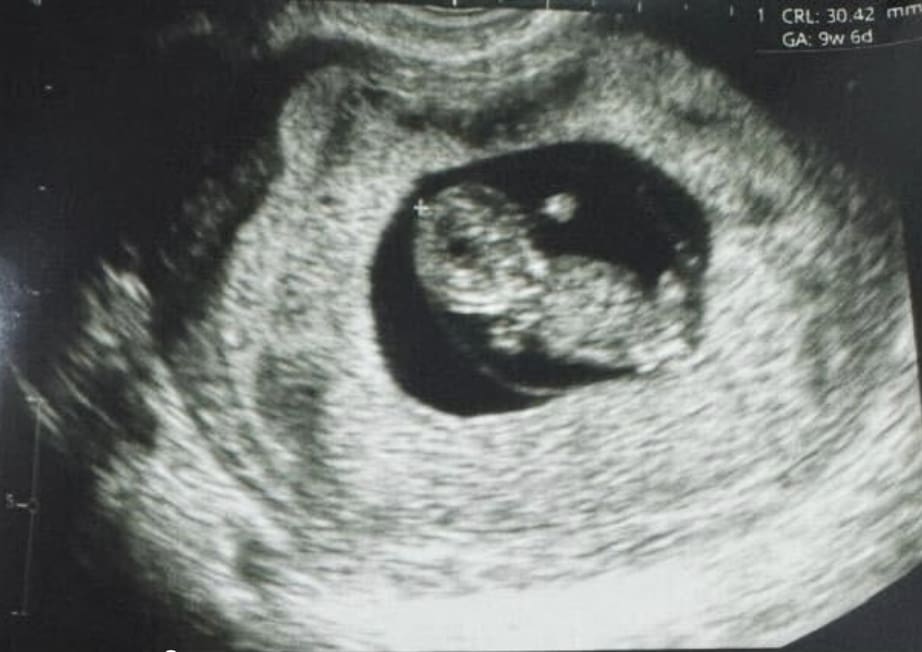

В Перу родился первый в мире ребенок, зачатый по технологии поддержки яичников (OSC), которая позволяет яйцеклетке созревать вне женского организма.